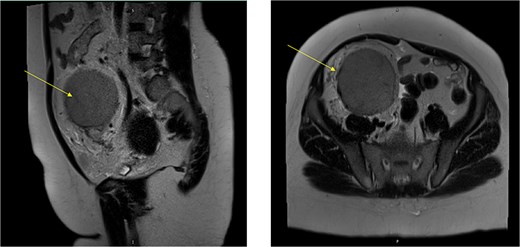

The MRI showed a large right iliac fossa extraperitoneal soft tissue mass, measuring 8.3 × 2.2 × 8.4 cm. The mass shows intermediate T2, low T1, and marked diffusion restriction. Dynamic imaging shows avid early contrast enhancement with retention of contrast in delayed imaging. The original spleen was in its normal place. The uterus showed multiple small intramural and subserosal fibroids with a low T2 signal, and an isointense T1 signal with no diffusion restriction or suspicious enhancement (Fig. 3).

MRI abdomen signifying the mass and its location, extent in both views (Arrow points at the mass).